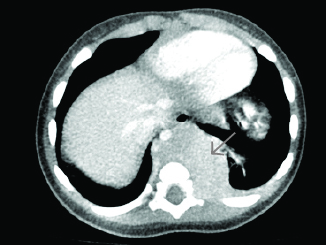

CT of the neck with IV contrast is the best study to identify abscesses in the retropharyngeal space. It can demonstrate extension of an abscess into contiguous spaces in the neck or chest and help differentiate between abscess and cellulitis. CT also can help identify the position of critical vessels in the neck when planning surgical intervention. (See Figure 4.)

Figure 4. CT Neck with Contrast Reveals Two Retropharyngeal Abscesses in an Intubated Patient |

Image courtesy of Derya Caglar, MD. |